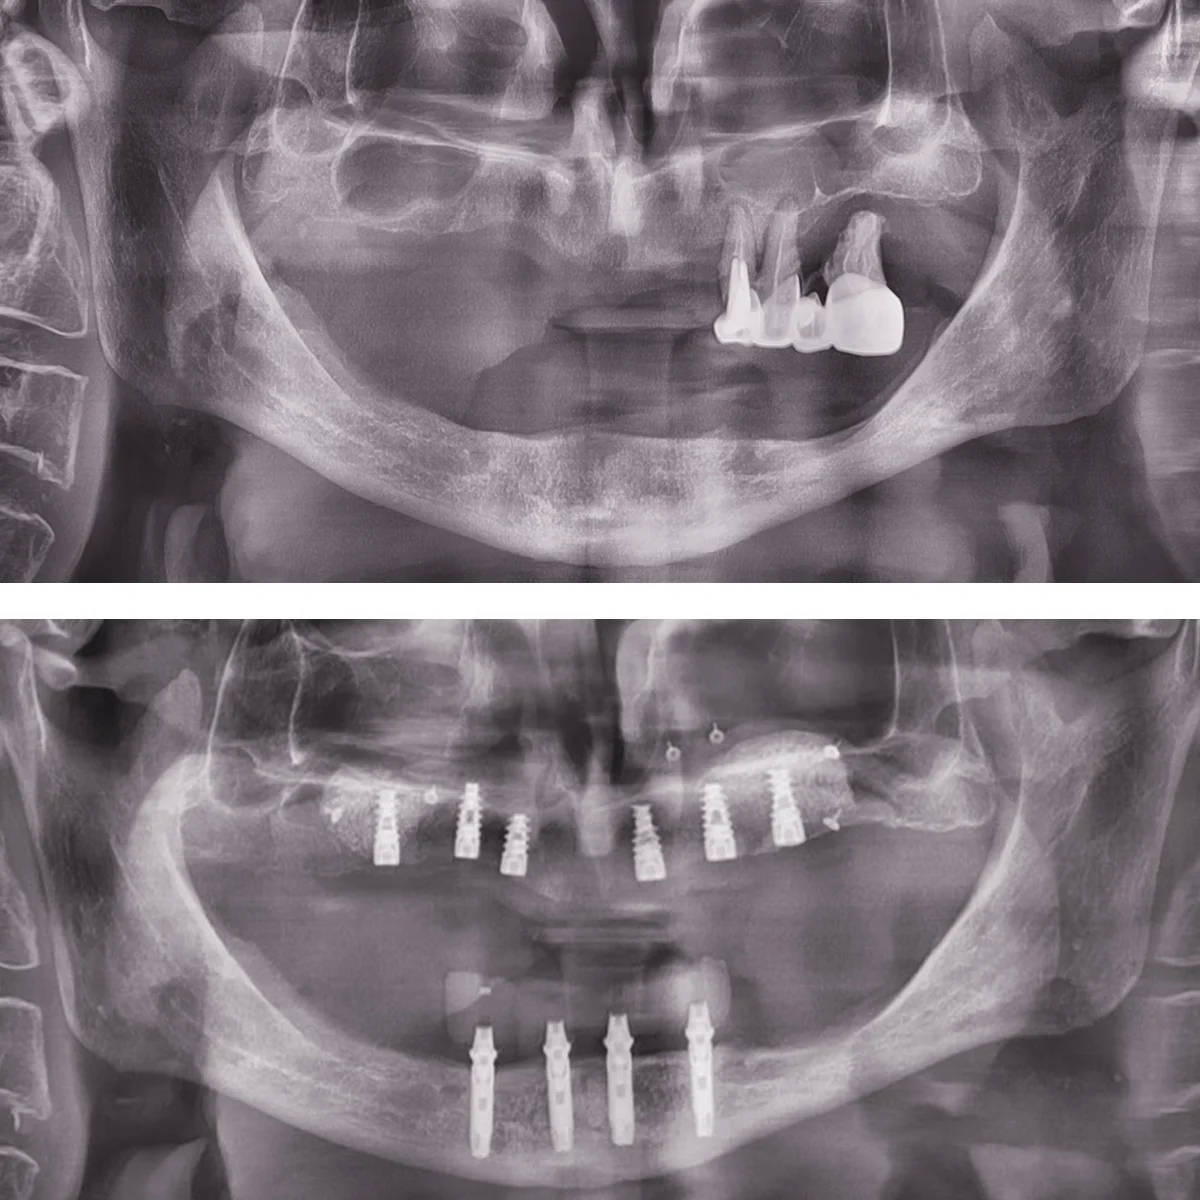

Dinți Ficși în 8-24 de ore pe implanturi dentare cu tehnica All-on-4/All-on-6 este cea mai eficientă și rapidă metodă de restaurare totală a danturii.

Intervenția chirurgicală explicată

Care sunt etapele până la efectuarea intervenției de dinți ficși

- Intervenția chirurgicală